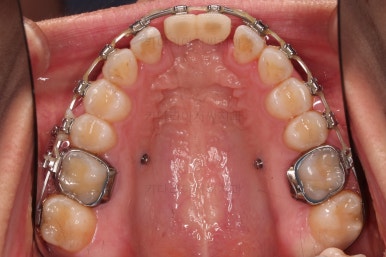

장치 부착은 윗니 어금니부터 했습니다.

미니스크류를 다양하게 활용하여 어금니 높이를 조절합니다.

여전히 앞니는 내버려둔 채로, 윗니는 어금니쪽만 진행하며 아랫니도 장치를 부착했습니다.

난이도가 매우 높은 치료인만큼 미니스크류의 구성과 장치 구성도 매우 복잡했는데요.

윗니 어금니를 뒤로 밀면서 앵글씨 2급 부정교합을 개선해 주고, 높낮이를 조절하면서 개방교합을 개선해 줍니다.

임플란트 뿌리 부분부터 식립이 되었습니다.

처음에는 언급드린대로 앞니 잇몸을 아래로 내리지 못한 점이 아쉽지만 발치 시점을 잘 선택하여 최대한 잇몸뼈를 보존했다는 점에서 만족스러웠습니다.

임플란트 머리 부분이 올라가기까지 기다리는 동안 좀 더 부산개방교합 디테일을 맞추고 마무리를 합니다.